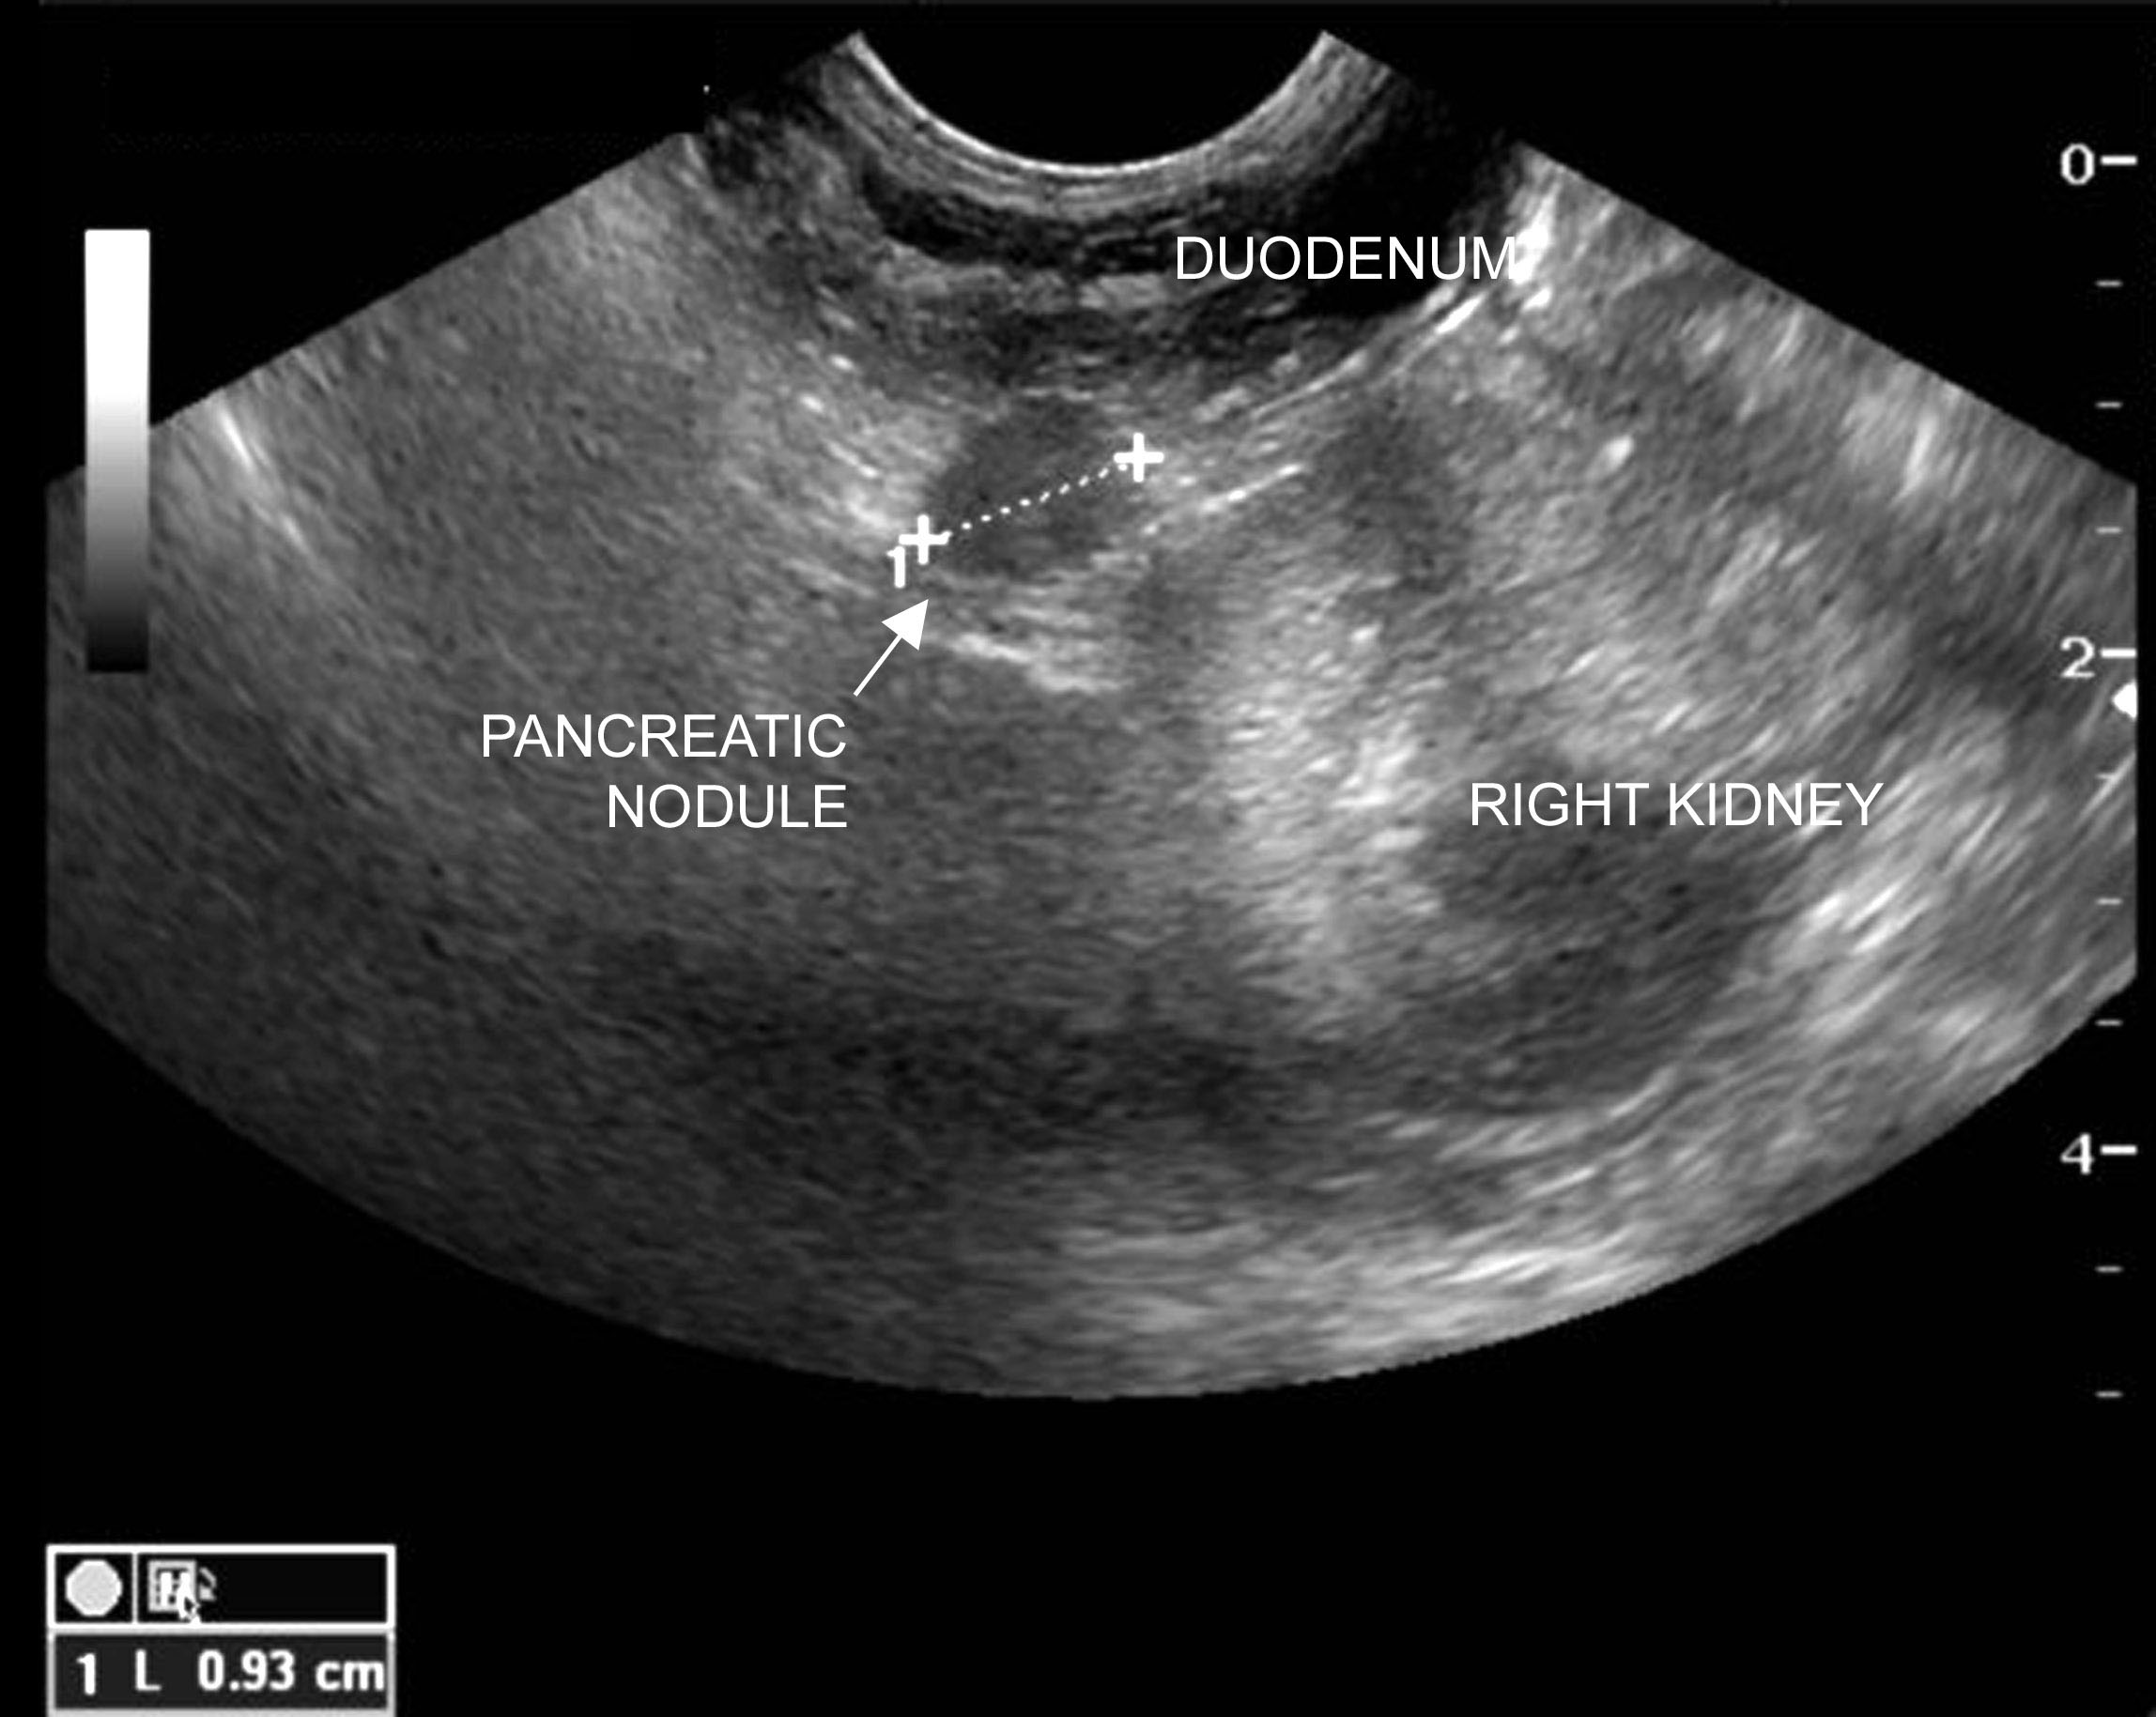

Differential diagnosis associated with different causes of

Episodes of Weakness Hypoglycemia in a Dog